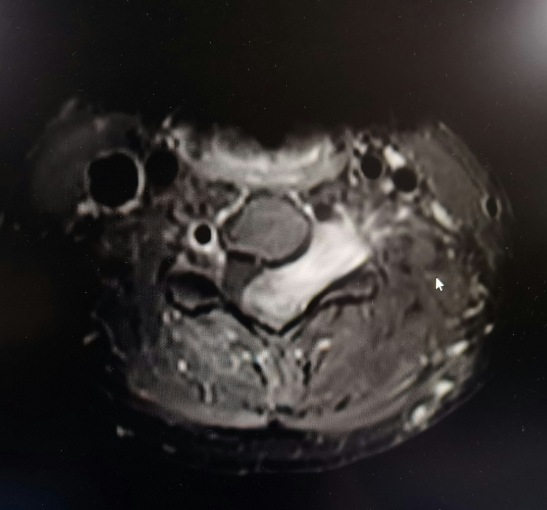

分娩的喜悦尚未淡去,李女士却频繁遭遇颈部疼痛和手臂麻木的困扰。起初,她以为这只是照顾宝宝过于劳累所致,并未予以重视。但随着疼痛日益加剧,夜不能寐,甚至出现了行走不稳症状。丈夫黄先生立即带她前往湘南学院附属医院进行检查。检查的结果令人震惊:她的颈椎管内脊髓及神经根被一个巨大肿块严重压迫,已经出现神经损伤表现,肿块如果继续生长可能导致瘫痪。脊柱外科团队结合患者的临床表现及检查结果,诊断为神经纤维瘤病。

神经纤维瘤病是染色体的遗传性疾病,发病率低,发生在颈椎椎管内的巨大神经纤维瘤更为罕见,且手术的难度、风险极高,稍有不慎就可能造成无法挽回的损伤。

面对这位年轻患者产后身体尚未完全恢复、肿瘤位置危险、情绪焦虑等诸多挑战,湘南学院附属医院脊柱外科团队,为李女士量身定制了一套详尽的手术方案。术中,专家团队运用显微外科技术,精准地切除了肿瘤,最大限度地保护了脊髓功能,同时避免了颈椎稳定性的丢失。术后第二天,李女士便感到症状明显缓解,手臂的力量逐渐恢复。